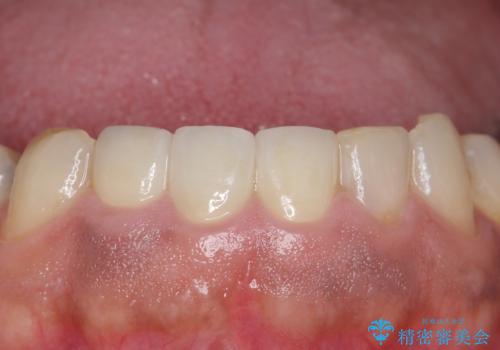

オールセラミッククラウンについて

今回用いたオールセラミッククラウンは、ジルコニアフレームという白い素材の上にセラミックを盛っているため審美性が非常に高いのが特徴です。

またジルコニアは人工ダイヤモンドの材料にも使われているほど高い強度を持っており、そのためオールセラミッククラウンは審美性だけでなく、奥歯やブリッジの補綴も可能とするクラウンです。